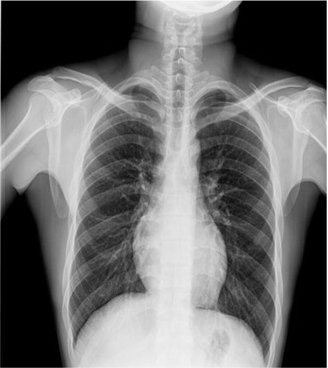

临床图片